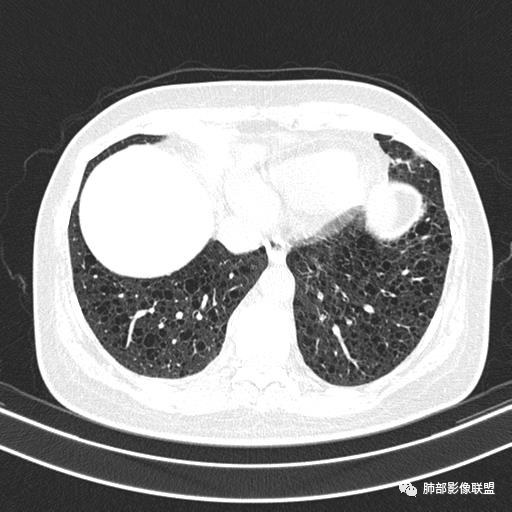

双肺弥漫囊腔,累及肋膈角,囊腔形态相对规则单一。

CT平扫示双肺弥漫分布大小不等囊状薄壁透光区,无内、中、外带分布差异,间质稍示增厚。拟LAM

中年女性育龄期妇女,咳嗽气喘,无吸烟史,有苯吸入史。影像:双肺弥漫均匀小囊腔,无明显分布优势,囊腔形态欠规则,壁薄,部分囊腔边缘血管征,伴双肺弥漫磨玻璃影,无结节,考虑lam,鉴别苯中毒肺损伤,囊腔多有分布优势,小叶中心分布为主,形态规整等

CT表现:双肺弥漫大小不等的薄壁囊腔,囊壁<2mm,外形规则,血管影多位于囊腔周围,囊腔之间肺组织正常,随着疾病进展到晚期,囊腔变大、增多,不可胜数,囊腔可融合成较大的囊,与肺气肿相似,形成间质性肺纤维化。部分病例可出现结节影。